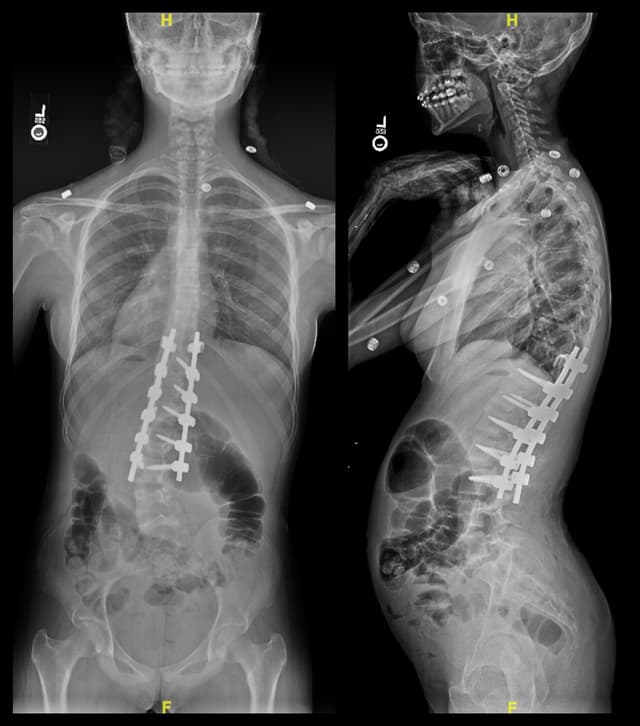

Posterior Spinal Fusion for Scoliosis

Imaging

Post-op